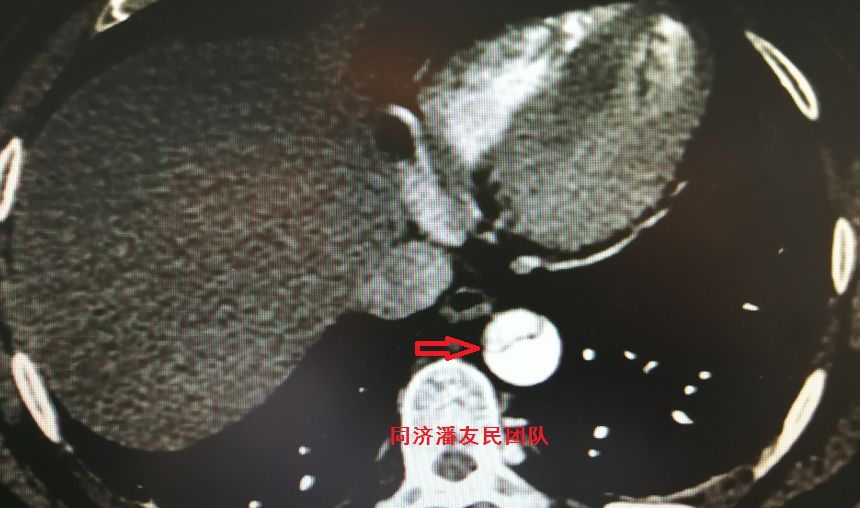

结果在上级医院复查胸腹主动脉CTA,在平扫CT提示主动脉夹层的对应层面,证实了主动脉夹层(图3~6)。同时发现升主动脉及主动脉弓均有夹层撕裂 (图7~8) 。 因此,正确诊断应该是 A型 (1型) 主动脉夹层。

图7 :CTA显示主动脉弓层面夹层撕裂内膜片(红箭头所示)

图8:CTA显示升主动脉及胸降主动脉均有夹层撕裂内膜片(红箭头所示)